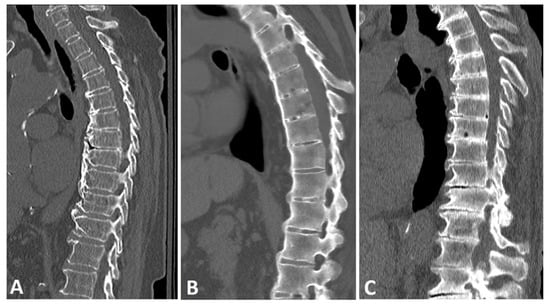

A characteristic feature of DISH is the presence of paraspinal flowing osteophytes resulting from the ossification of soft-tissue structures surrounding the vertebrae [1]. A lucent line extending between the vertebral body cortex and the osteophyte distinguishes these paraspinal osteophytes from degenerative, marginal osteophytes, which are an integral extension of the vertebral endplate, and from SpA-related syndesmophytes, which result from ossification of Sharpey’s fibers of the annulus fibrosis (Figure 1) [23].

Figure 1.

Sagittal CT reconstructions of the thoracic spine in three different patients: (A) a patient with DISH with thick, flowing, horizontally oriented, coarse osteophytes; (B) a patient with AS with slender, vertically oriented syndesmophytes; and (C) a patient with degenerative disc disease with horizontally oriented, non-flowing osteophytes. Note that the disc space is relatively preserved in the DISH subject, but not in the patient with a degenerative spine.